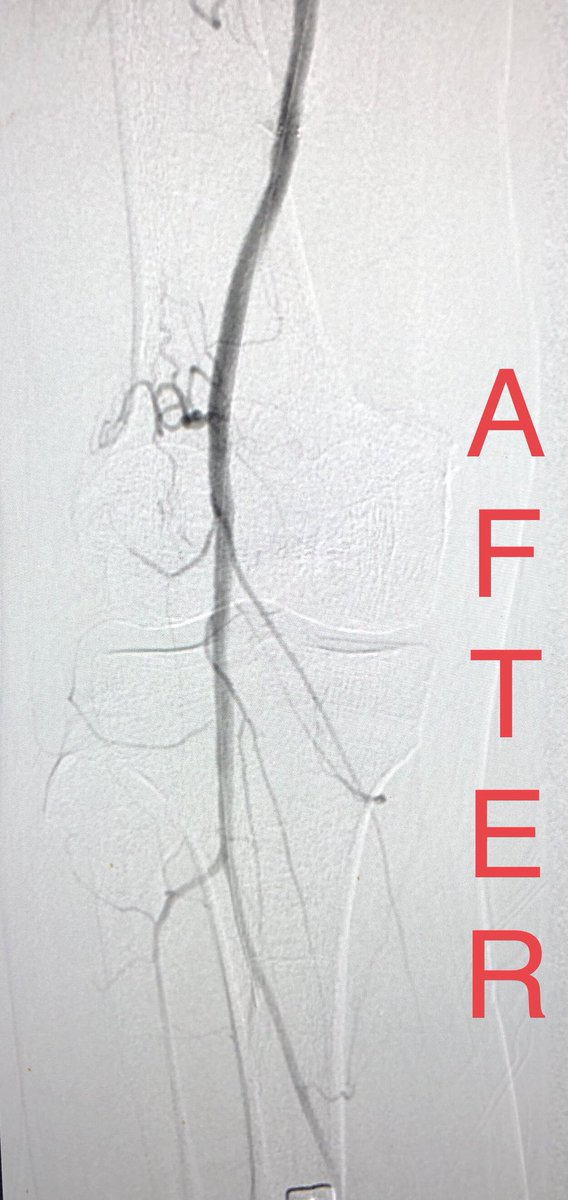

What to do when you can’t get through a distal anastomotic stricture of a thrombosed fem-pop bypass despite lysis? Just open up his native SFA! Special thanks to my fellow, Yusuf @yhkarrar ! UICOMP Radiology SIR RFS Society of Interventional Radiology @

What to do when you can’t get through a distal anastomotic stricture of a thrombosed fem-pop bypass despite lysis? Just open up his native SFA! Special thanks to my fellow, Yusuf @yhkarrar ! <a href="/UICOMPRadiology/">UICOMP Radiology</a> <a href="/SIRRFS/">SIR RFS</a> <a href="/SIRspecialists/">Society of Interventional Radiology</a> @